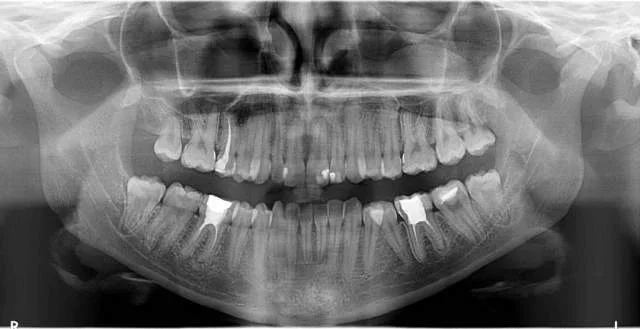

Shitet grafi dentare panoramex dhe cefalometri sirona xg 3d. Prodhim i vitit 2016 . Nje vit garanci Cel. : 0683869777

Shitet Panorameks 2D/2D+ Carestream (Kodak) Aparati është në gjendje shumë të mirë si nga ana vizuale dhe nga ajo funksionale. Ka edhe opsionin...